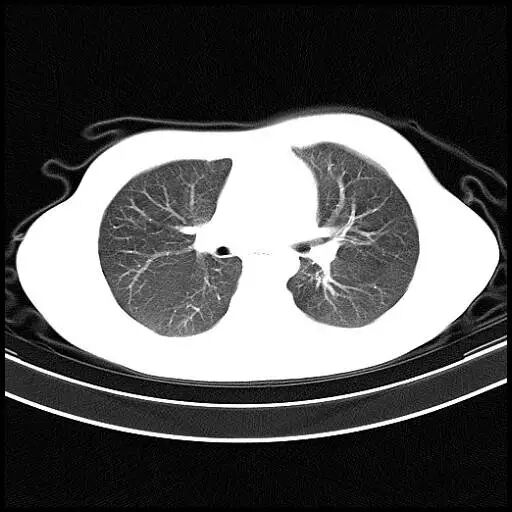

正常肺的CT表现

图片

图3

胸廓的横径和前后径的比例是3:2,双肺纹理走行自然,像树杈一样分支越来越细,直达肺的边缘,肺野内未见异常密度影。正常的肺泡直径平均只有0.2 mm左右,CT是看不见的。